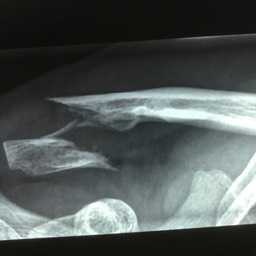

What do clavicle fractures look like on X-ray?

Below are examples of typical fractures that benefit from surgery.

Click an image to enlarge